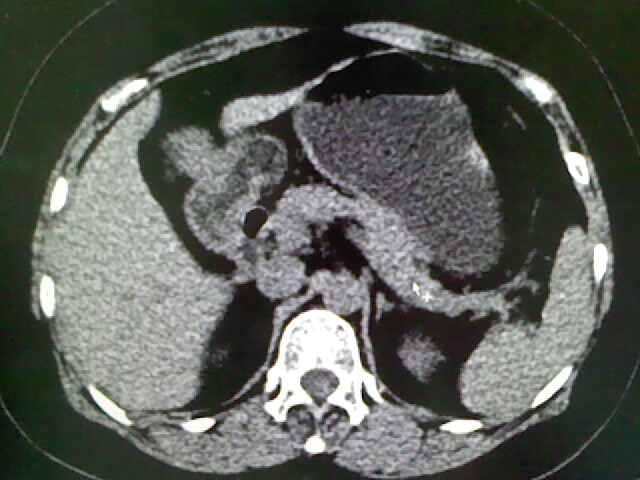

以下是引用liaoqiang在2009-4-2 16:23:00的发言:[br]胆囊是否切除?胆囊颈区致密影考虑金属夹?结石?肝脏右叶低密度影,考虑增强。

以下是引用卜一在2009-4-2 13:26:00的发言:[br]胆囊颈部结石伴胆囊炎!另:建议增强,待除外肝内占位及胆囊占位!